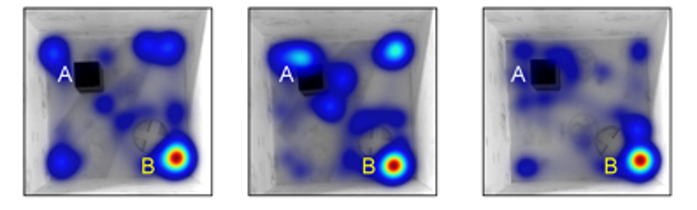

- 연구주제 : 근육-뇌 신경회로 역할 규명을 통한 인지기능 및 근감소증 제어연구

- 연구주제 : 장-뇌 축 신경회로 제어를 통한 염증 및 인지기능 개선연구